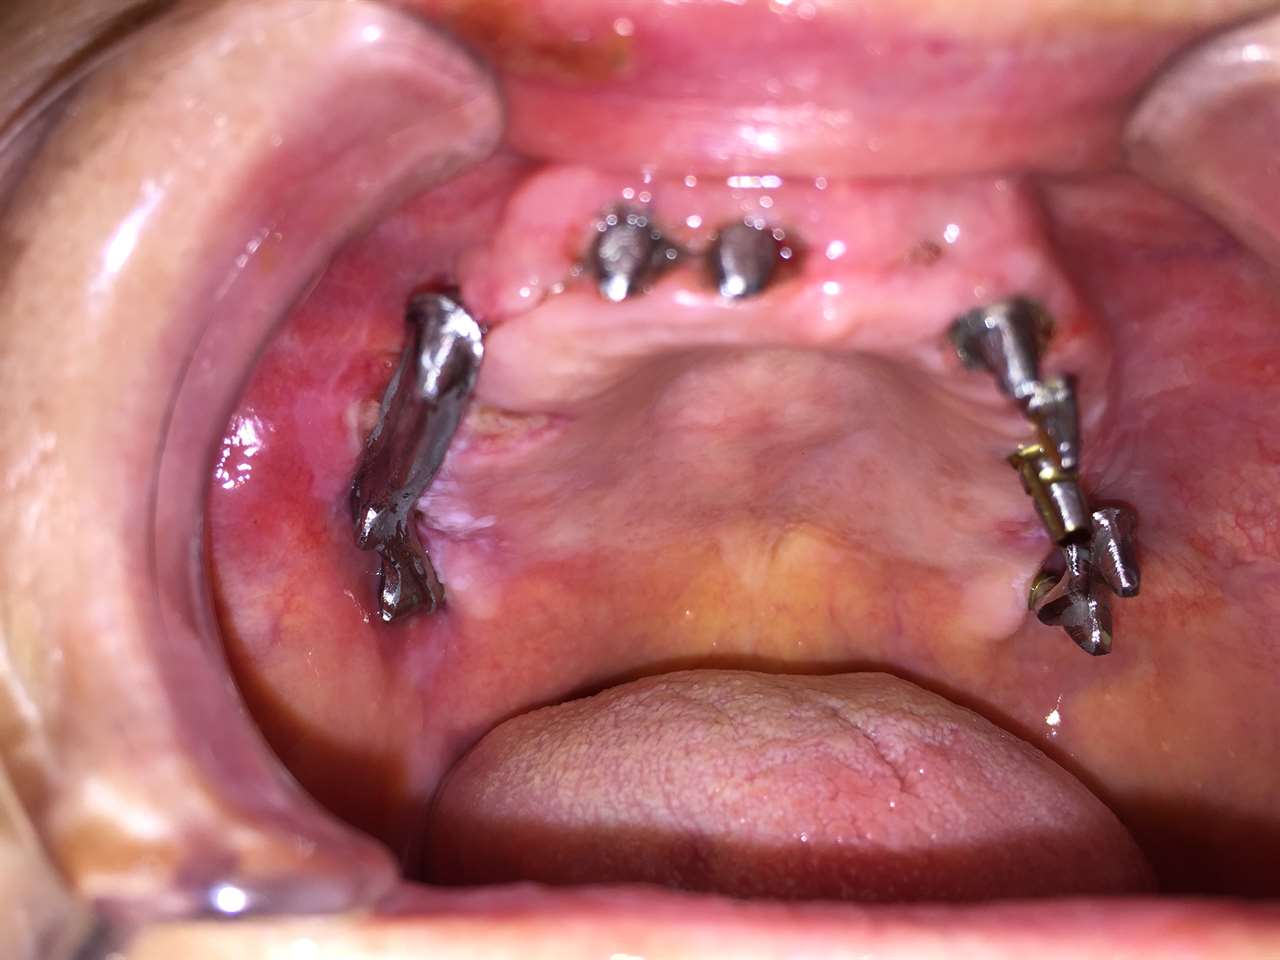

Alsó állcsont teljes rehabilitációja 72 óra alatt

Alsó állcsont teljes rehabilitációja 72 óra alatt, azonnal terhelhető implantátumokkal súlyos paradontitisben szenvedő dohányzó páciens esetében. Az alsó állcsont fogai mind mozogtak az előrehaladott fogágypusztulás miatt.

A fogakat eltávolítottuk, a gyulladt, fertőzött csontot kitakarítottuk, kifertőtlenítettük, majd azonnal implantáltunk.

Svájci, IHDE márkájú, azonnal terhelhető implantátumokat helyzetünk be, és ezekre harmadnapra rögzített, hosszútávú, fémvázas, esztétikus műanyaggal leplezett hidat ragasztottunk be.

Ezt az ideiglenes hidat a sebek gyógyulása miatt használjuk, de tartóssága miatt véglegesként is használható.

A legtöbb esetben, ahogy itt is, 6 hónap múlva porcelán hídra cseréljük, a teljes gyógyulás után.